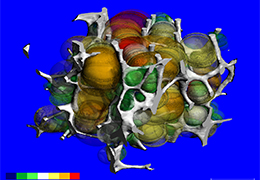

High-quality and fast 3D reconstruction and 3D rendering

Performs 3D reconstruction and volume rendering.